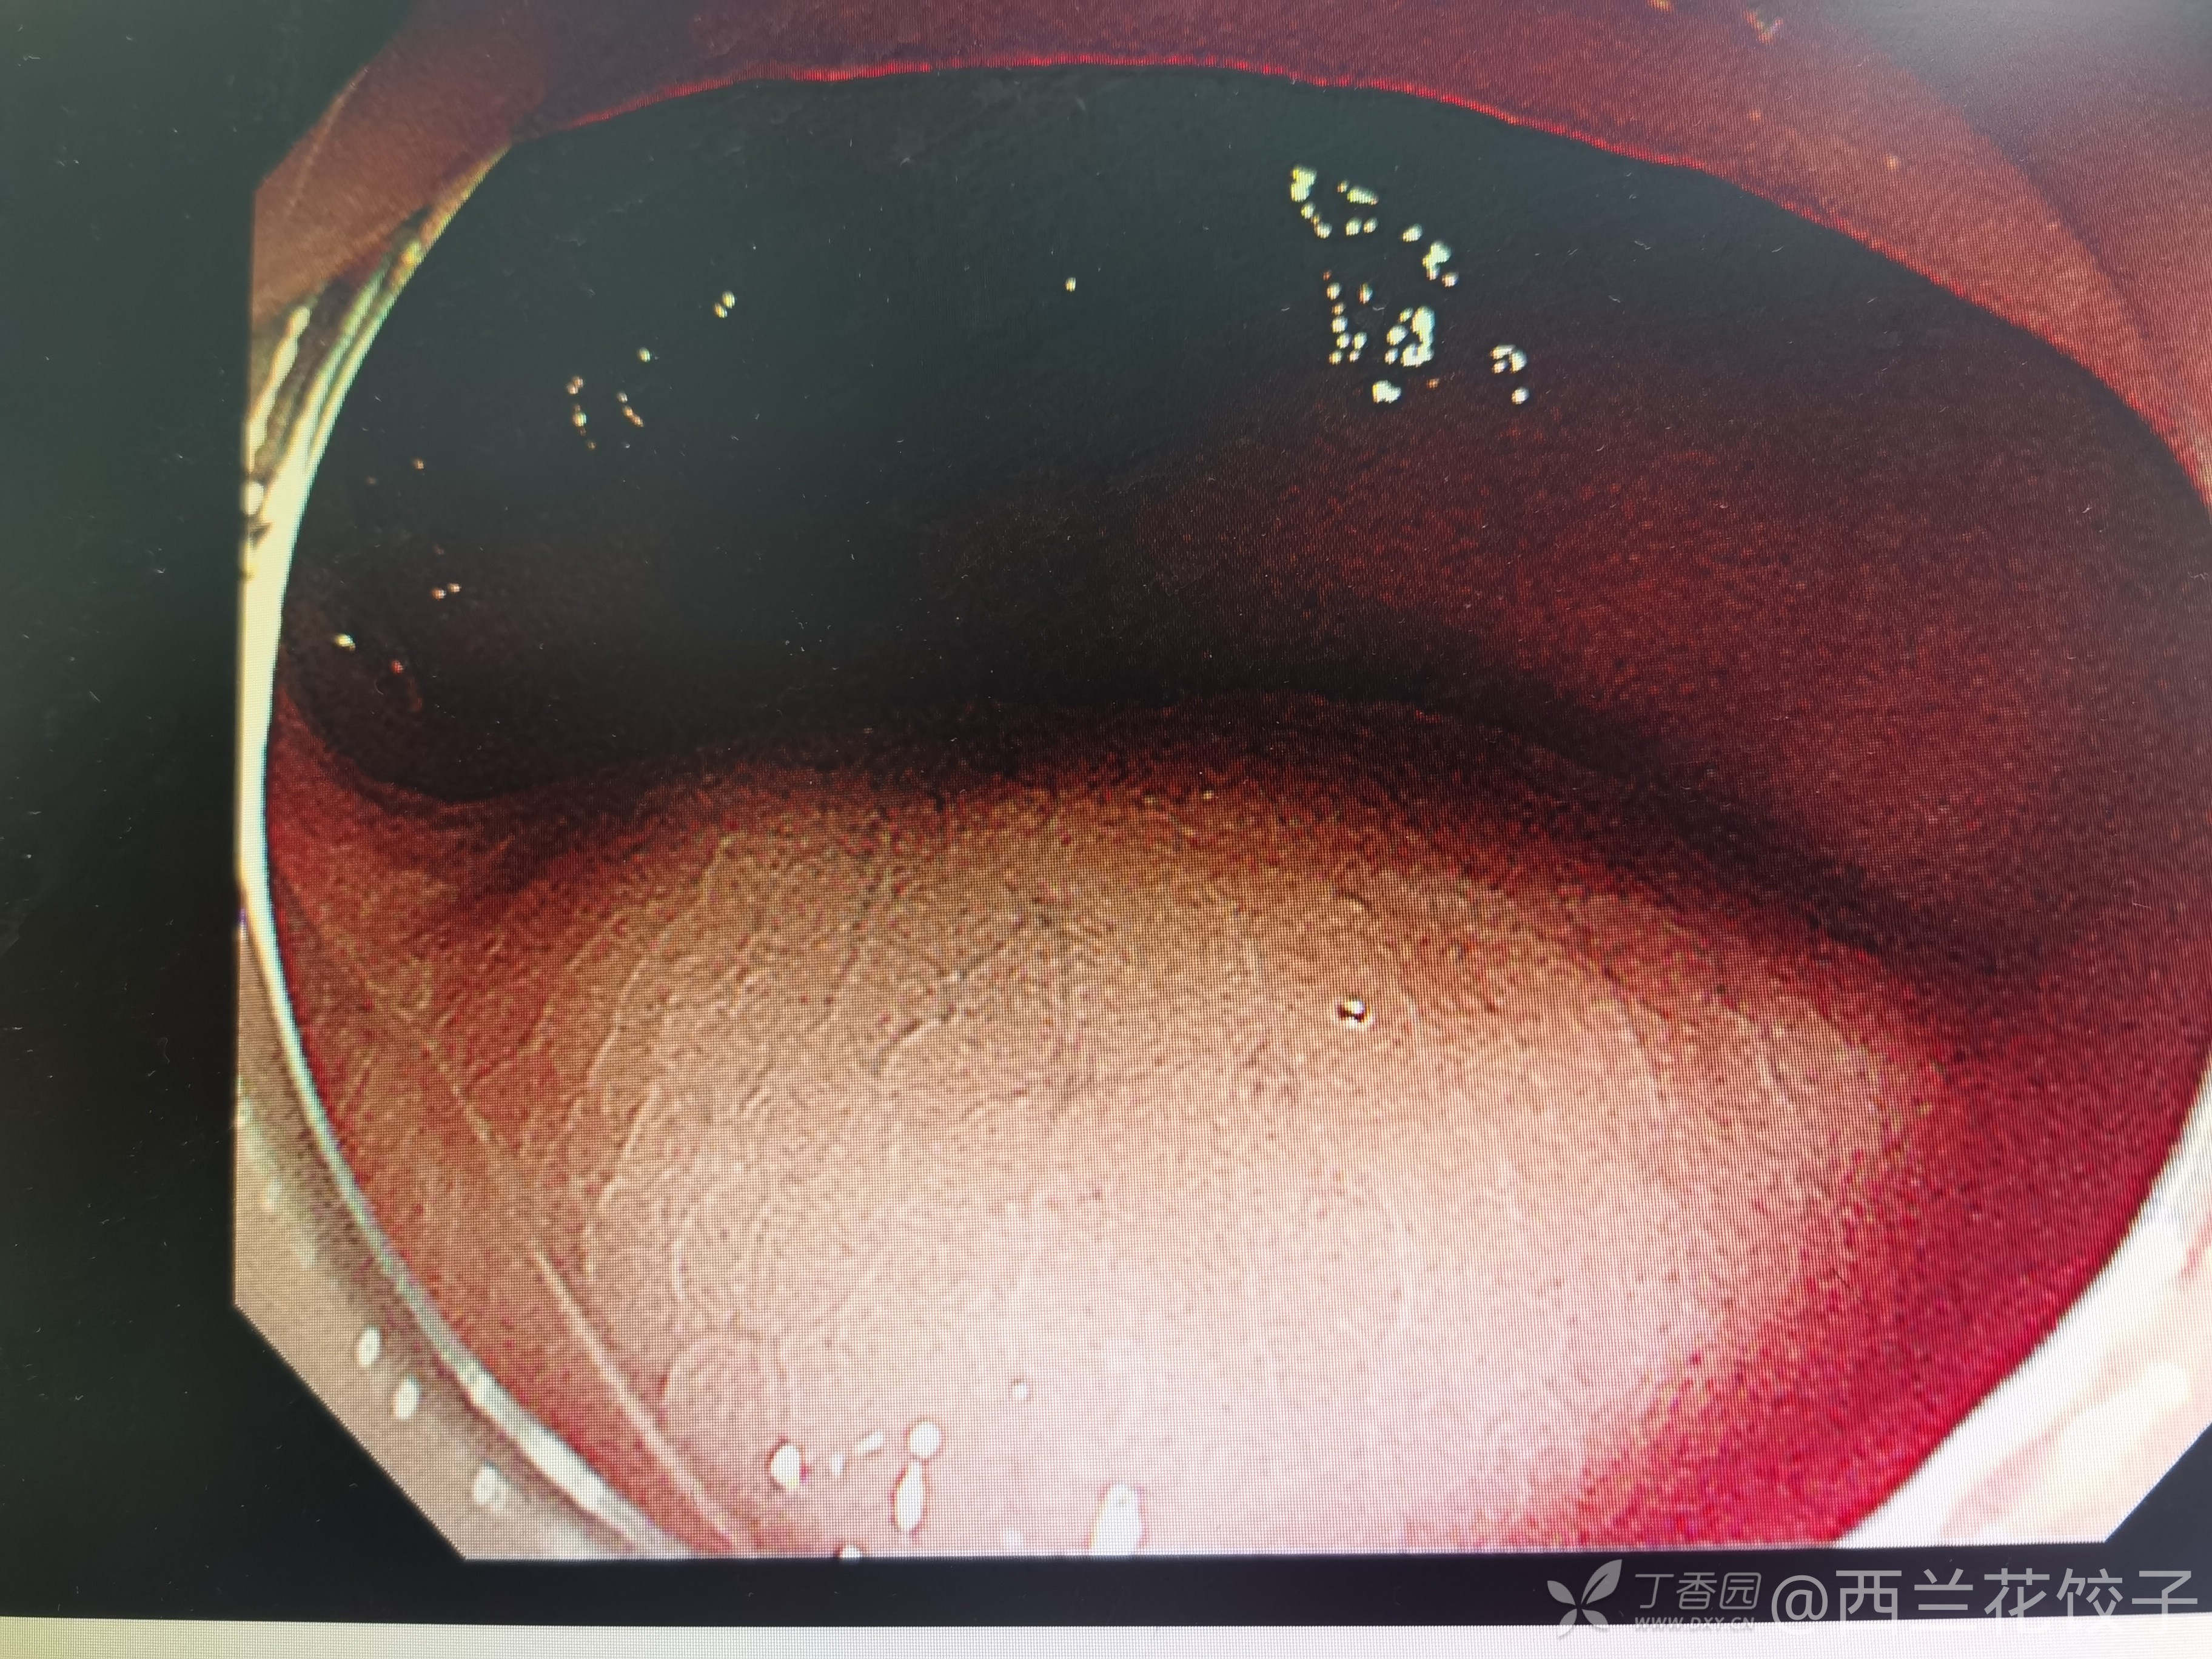

主诉:发现直肠肿物1周

简要病史:患者因便秘外院检查发现直肠肿物遂来我院治疗,既往有结肠黑变病病史多年。

辅助检查:肠镜检查及超声如下

讨论:你觉得可能是什么,如何治疗?